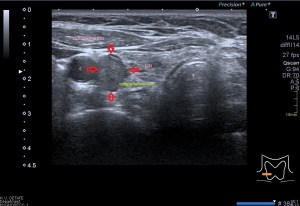

Con la eco pasa igual…cuando queremos estudiar, por ejemplo, el recto anterior del muslo en axial,perfecto…pero en longitudinal, como la imagen 2, se complica porque desde la rótula a la inserción en la cadera, tenemos mucho recorrido. En este caso hacemos lo mismo que cuando hacemos la foto del atardecer…nos ponemos en un extremo, activamos la funciona, recorremos suave y continuamente por la anatomía que queremos fotografiar y ya está…mira la pantalla y no el movimiento de tu mano,como si hicieses la foto, ves la pantalla,pero no como mueves el teléfono.

Es muy útil para lesiones que han crecido mucho y no podemos conjugar en una sola imagen, por ejemplo, un lipoma, cuando superan la medida de la huella de la sonda no son medibles, hay que usar «panoramic view», y como este caso, otros muchos.

Técnicamente es lo mismo, ambos dispositivos hacen una suma de imágenes que se plasman en un resultado final estupendo. Toda la escena más pequeña, pero más alargada que te da percepción de toda la magnitud de aquello que pretendes estudiar, te quita algo de detalle, pero te sirve para medir perfectamente y además puedes incrementar y mover la imagen con tu track ball…

Podemos medir valores superiores a los 15cms con alta calidad de imagen…podemos llegar a medir valores por encima de los 25 cms…es verdad que no todos los equipos tienen este ajuste ecográfico, es decir, es una aplicación y por tanto hay que pagarla.